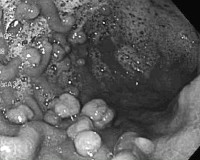

• Эзофагогастродуоденоскопия. Эндоскопическое исследование верхних отделов пищеварительного тракта оценивает состояние слизистой оболочки и показывает типичные полипозные разрастания эпителия. Биопсия измененных областей проводится для цитологического исследования тканей.

Если у пациента синдром дистального колита, целесообразно обследовать толстую кишку с помощью гибкого эндоскопа. Во время обследования врач обнаруживает диффузный полипоз, отбирает биопсию для гистологического анализа и, в зависимости от показаний, проводит терапевтические мероприятия (гемостаз, резекция).